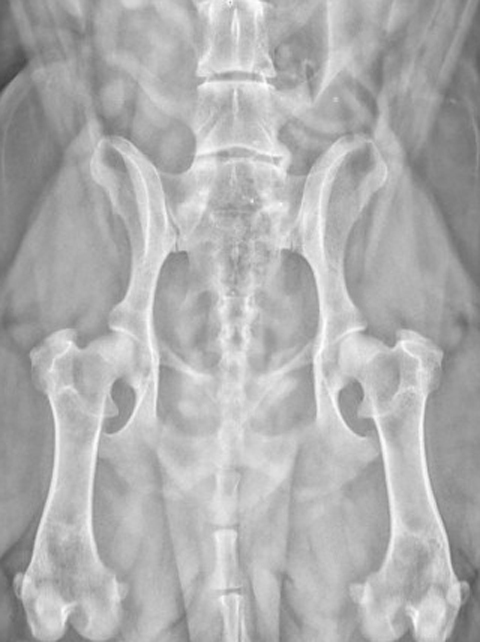

ДТБС у собак: рентгенограммы

ДТБС: степень "D" — средняя форма